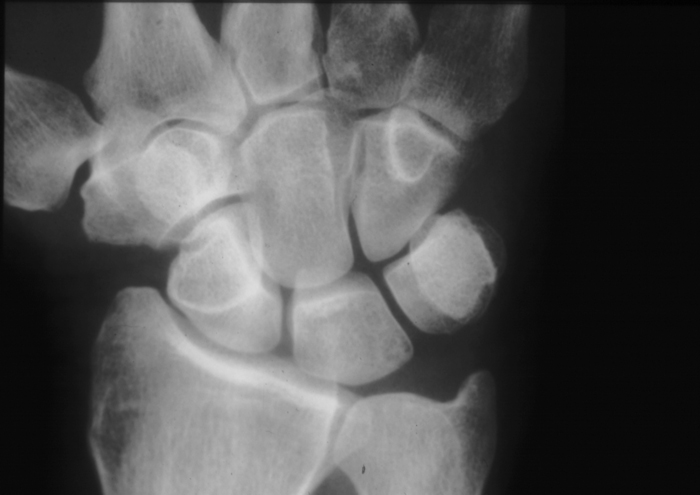

Radiology MS 32 - Normal Wrist

Identify: radial styloid, ulnar styloid, navicular (scaphoid), lunate, triquitrum, pisiform, trapezium, trapezoid, capitate, hamate, all metacarpals